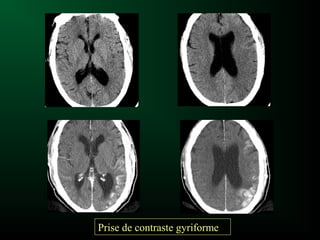

– Rupture de la barrière hémato-encéphalique : Prise

de contraste corticale gyriforme au stade

intermédiaire (5j-5sem)

Ischémie cérébrale et Scanner

Effet de masse

Prise de contraste gyriforme